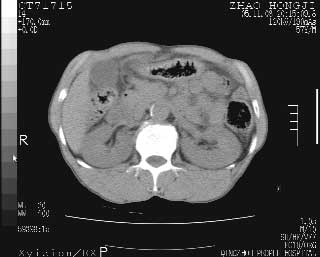

肝脏前缘见少量积气、胰尾部见少许气体包饶,肾前筋膜未见增厚,临床淀粉酶不高,意见:上消化道穿孔。

消化道穿孔。12指肠球部周和胰周积气考虑12指肠穿孔可能性大。

入院3小时后行剖腹探查术,见腹腔内大量脓性混浊液约1000ml,十二指肠球部溃疡穿孔,溃疡面约2.5x2cm,穿孔直径约0.6cm。胃内容物外益,周围组织炎性水肿明显。行十二指肠穿孔修补术。术后诊断:

1、十二指肠溃疡穿孔

2、弥漫性腹膜炎

对于少量的腹腔游离气体,ct检查较普通透视有绝对的优势,它不仅可以看到肝脏前上缘的气体,而且还能够看到小网膜区的游离气体。从而可以肯定诊断。各位分析战友的很好,感谢大家的参入!